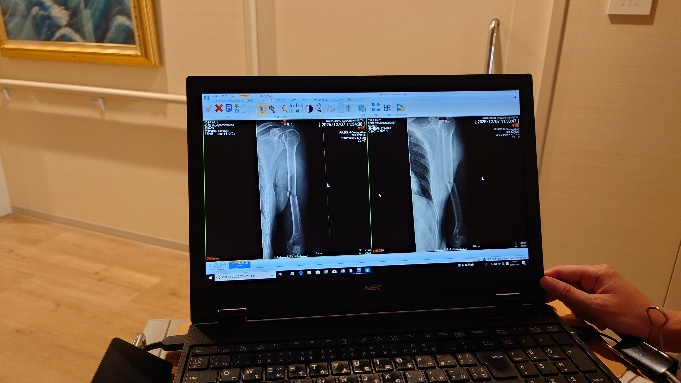

気づくと救急車は止まり、ゴーっといううなりと共に後部のハッチが開いた。恐怖と後悔に満ちた世界へと強制的に連れ出される。一瞬の光を浴びるもすぐに予定された暗黒世界へ入り込む。奥の救急外来待合室でしばらく待つ。他に誰もいない。静けさがこれからの不安をかきたてる。優しい長女はまだ一緒だ。ついに診察室へ呼ばれる。裁きはこれからだ。のろのろと車いすが押され、柔和な閻魔様の前に引き出される。簡単な診察のあとレントゲン写真を撮りすぐに結果が出た。

再びホワイトグレーの寡黙な裁判官が口を開く。判決は「入院しましょう。」そのほか手短だが色々お話をして下さるも痛み止めで注意力と記憶力の低下した脳は理解しないまま次のシーンへ飛ぶ。

ちなみに自分の左腕はいない。今回大暴れした気の毒なやつを除いて。最後のレントゲン写真撮影と退院手続きを早くに終わらせ病室で荷物をまとめた。大した量ではないが、小さなビニール袋一杯分にはなった。